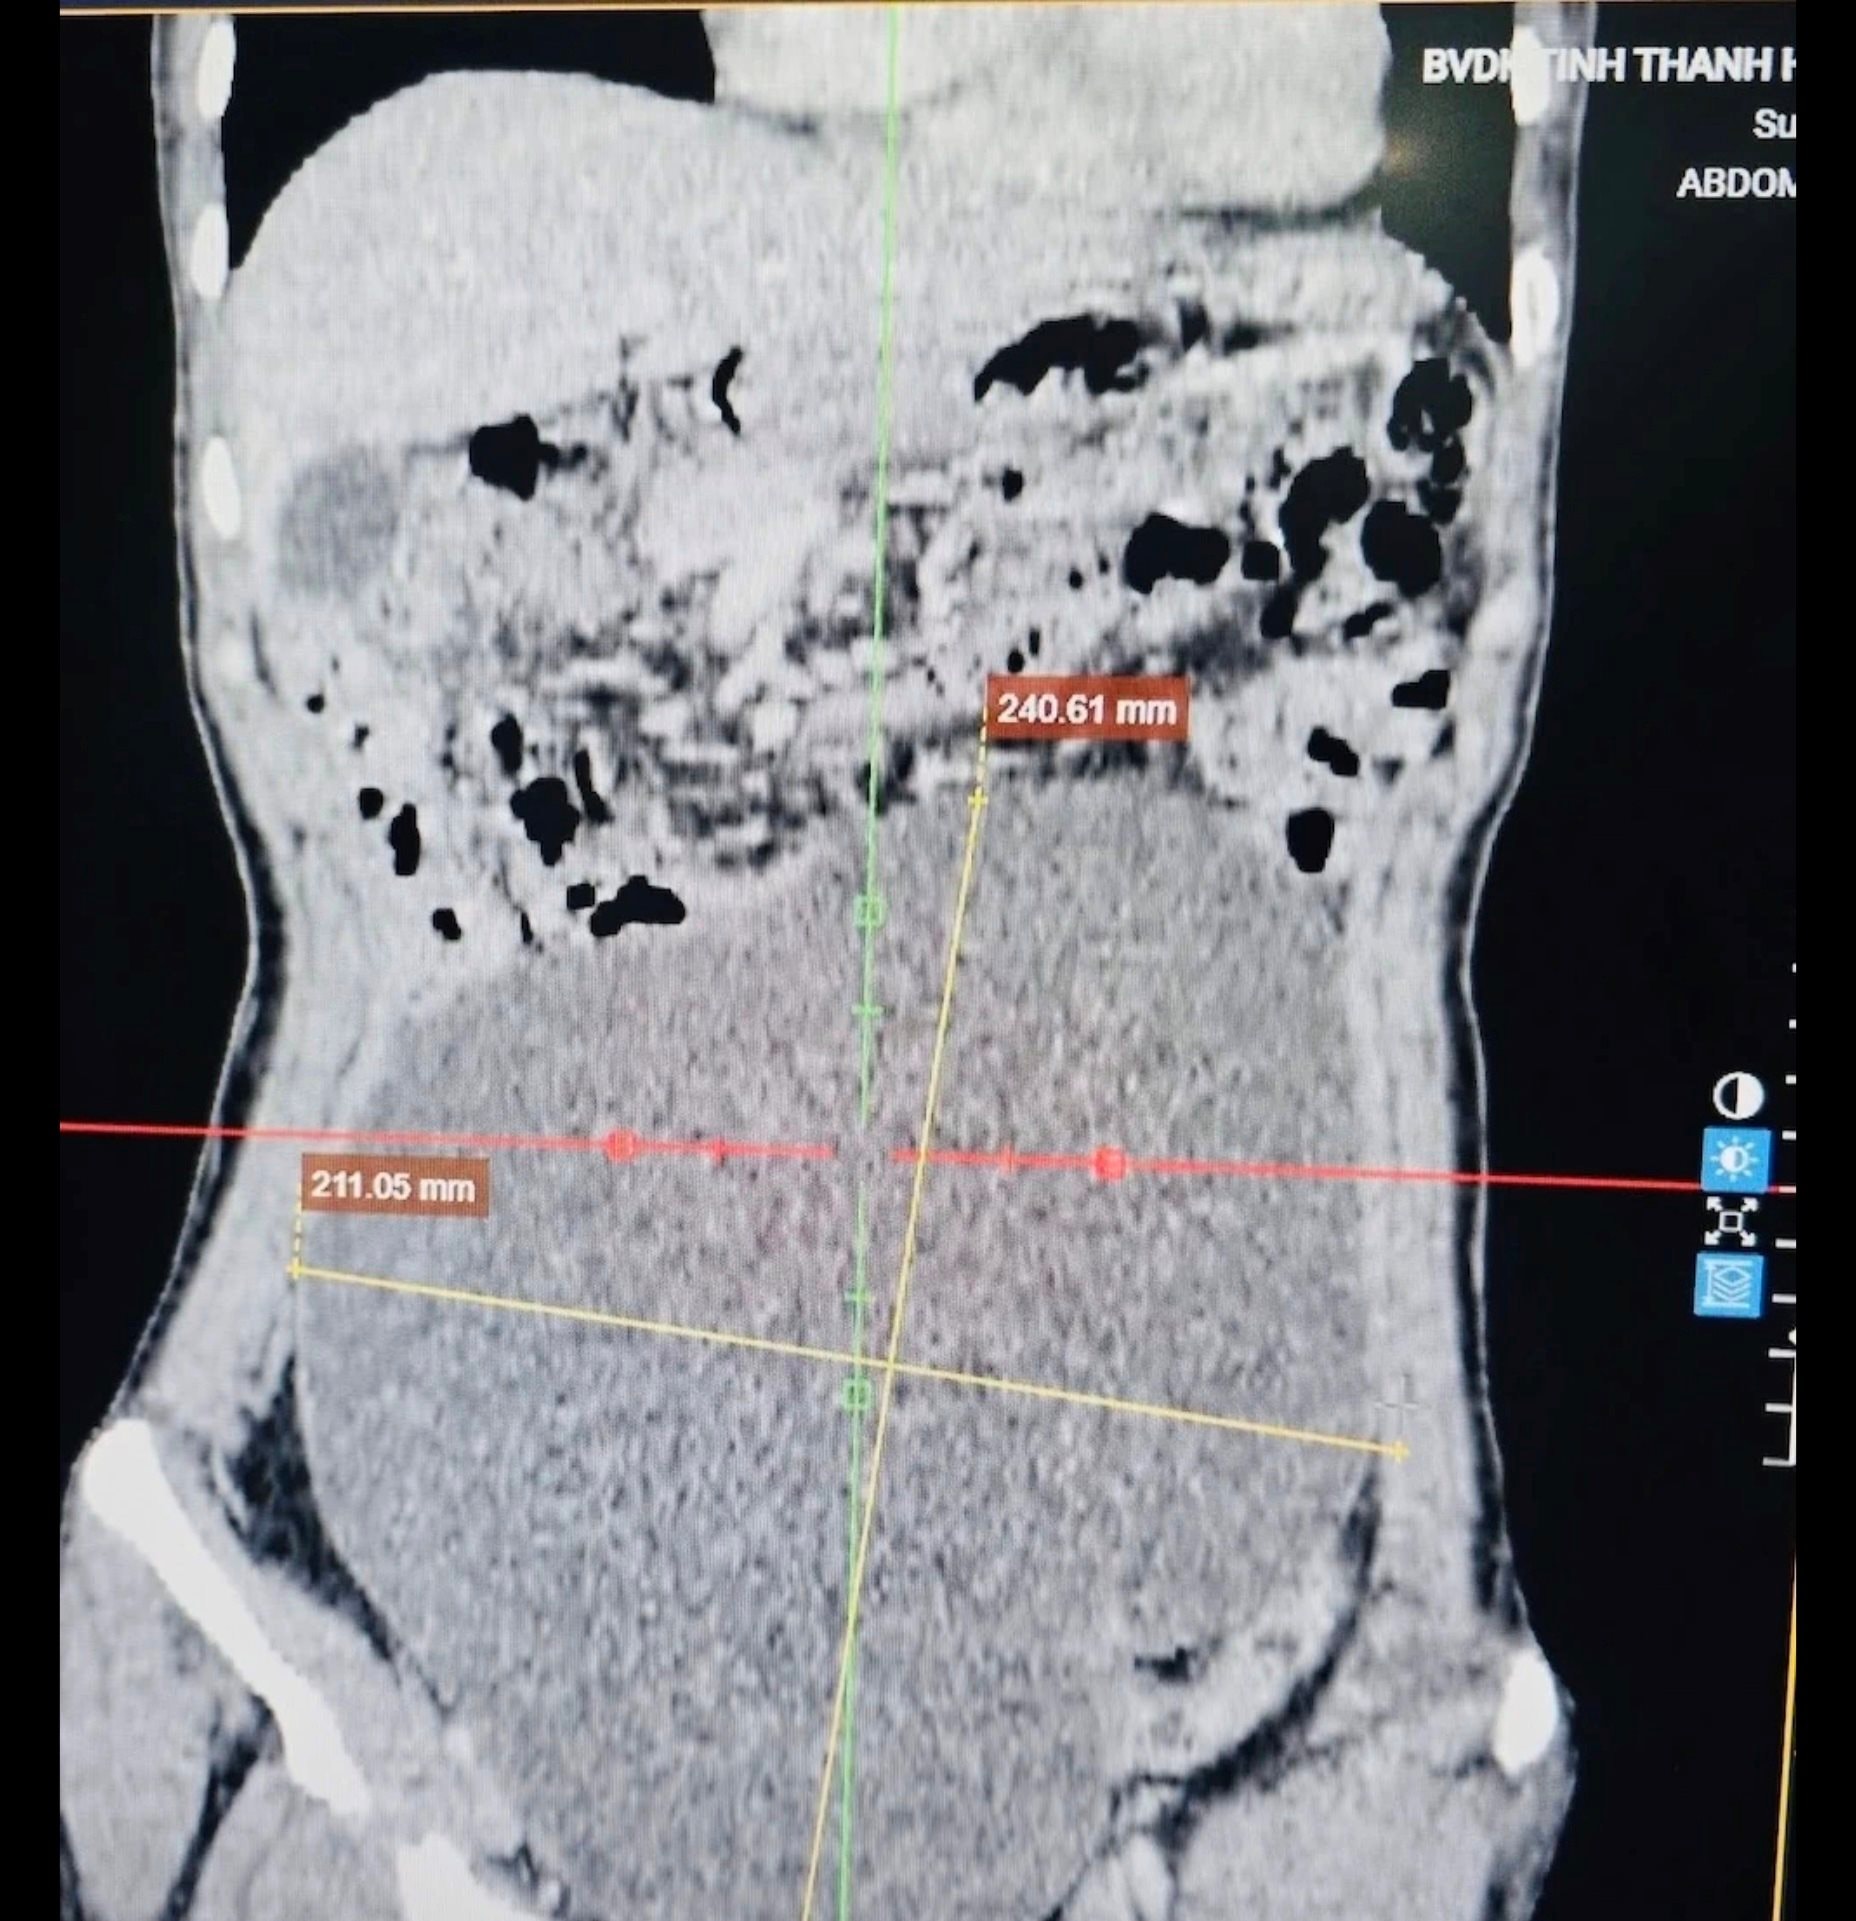

Tại bệnh viện, kết quả chụp cắt lớp vi tính (CLVT) ổ bụng cho thấy một khối u kích thước rất lớn, chiếm gần toàn bộ ổ bụng, kéo dài từ hạ vị đến thượng vị, xuất phát từ buồng trứng.

Hình ảnh khối u trong cơ thể nữ bệnh nhân.

Ca phẫu thuật được thực hiện bởi ê-kíp Khoa Ngoại tổng hợp 2 phối hợp với Khoa Gây mê hồi sức, đã bóc tách thành công khối u xuất phát từ buồng trứng trái, kích thước khoảng 25cm, nặng gần 3kg.